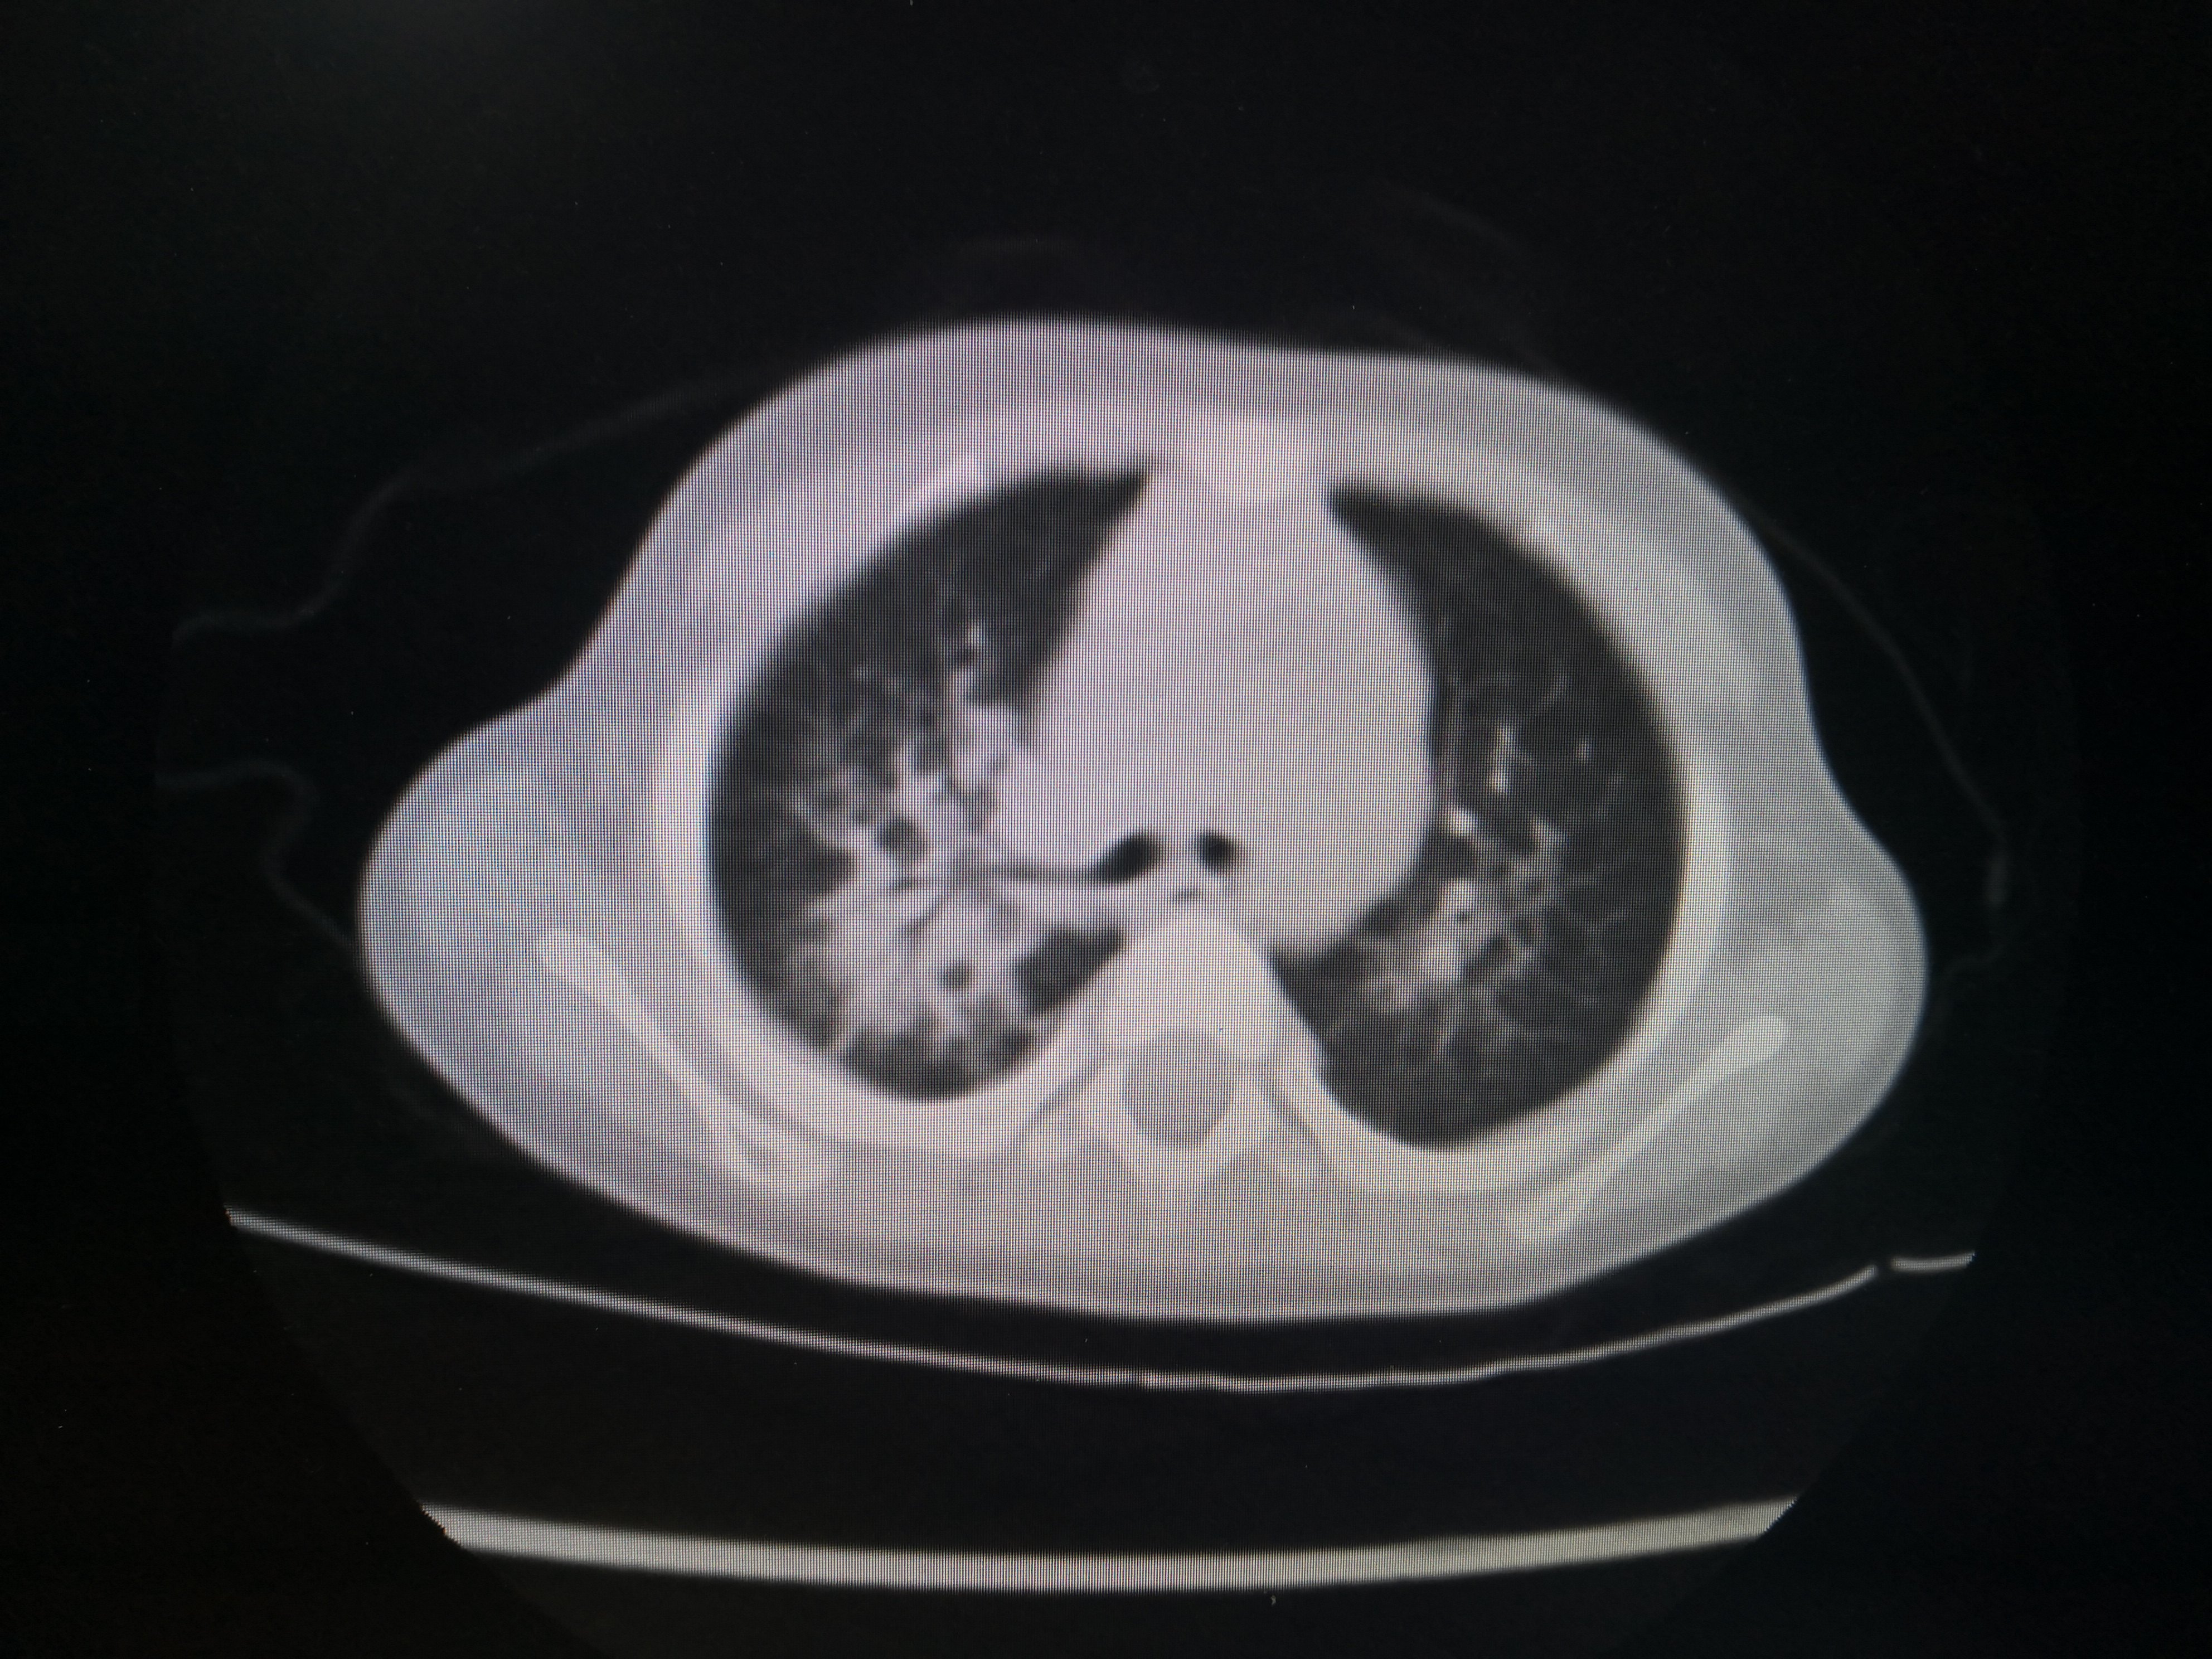

某小朋友1岁多,家住农村,在玩耍的时候不慎坠入粪池,该粪池深1.5米,不到一分钟该小朋友就已经被粪池漫过头顶仅剩一只手在外面,幸运的是旁边有大人及时发现并立即将其从粪坑里拔出。但是整个救援过程将近10分钟,小朋友被救出时已经失去意识,处于昏迷状态,急诊送至当地县医院清洗后立即120送至重庆医科大学附属儿童医院呼吸一科。入院时小朋友已经清醒,但是高烧不退,炎症指标非常高!入院后积极予以强有力的抗生素抗感染,并完善胸部CT评估双肺吸入性肺炎的严重程度,如图1

双肺炎症非常明显。CT结果出来后立即予以支气管镜灌洗治疗,在灌洗治疗过程中发现小朋友气管支气管里面大量黑色粪渣伴有较多黄色粪汁,遂将每个肺叶肺段灌洗干净,一周内完成2次支气管镜的灌洗治疗。第二次灌洗的时候双肺已经比较干净。出院后又口服了两周的强力抗生素。两周后复查胸部CT,结果如下